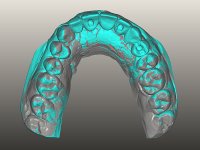

O paciente foi observado conjuntamente e a dúvida que surgiu de imediato foi se seria possível com a regeneração óssea a efectuar poder ser reabilitada naturalmente a zona das papilas interdentárias. Nesse sentido foi feito um enceramento de diagnóstico que contemplaria as duas hipóteses, utilizando ou não a cerâmica gengival. A confecção desse enceramento foi fundamental para expor ao paciente a dificuldade da reabilitação. O wax-up deu origem a um mock-up que foi aprovado pelo paciente e que simultaneamente serviu de guia imagiológica. O caso foi planificado cirurgicamente e realizada uma guia cirúrgica com que foram colocados os implantes. Após 10 semanas foi feita a 1ª impressão para confecção da ponte provisória. Foram criados os primeiros perfis de emergência na gengiva artificial e foi digitalizado o modelo. Por processo de CAD-CAM foi confeccionada uma ponte provisória aparafusada baseada no enceramento de diagnóstico. A ponte trabalhou durante 8 semanas os tecidos moles que foram fielmente copiados numa impressão com técnica de moldeira aberta. Os transferes foram individualizados com resina composta para copiarem fielmente os perfis de emergência criados pela ponte provisória. Confeccionado o modelo de trabalho definitivo, foi realizada uma infra-estrutura em zircónio seguindo a orientação do enceramento de diagnóstico. O assentamento da infra-estrutura foi testado em boca e simultaneamente foi novamente impressionados os tecidos moles com um silicone fluido. Nessa consulta foi feito o levantamento da cor. Os dentes 13 e 23 apresentavam uma saturação anormalmente forte que resolvemos não valorizar, optando por privilegiar a relação com o sector antero-inferior. Foi realizada uma nova gengiva artificial com a impressão que acompanhou a impressão de arrasto com a infra-estrutura. Após a colocação da cerâmica na infra-estrutura foram coladas as meso-estruturas. O trabalho final foi aparafusado lentamente permitindo a adaptação dos tecidos moles.